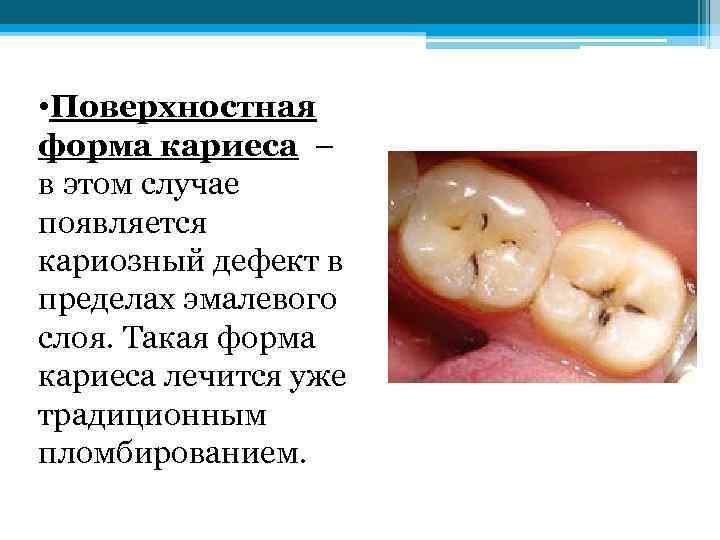

• Поверхностная форма кариеса – в этом случае появляется кариозный дефект в пределах эмалевого слоя. Такая форма кариеса лечится уже традиционным пломбированием.

• Поверхностная форма кариеса – в этом случае появляется кариозный дефект в пределах эмалевого слоя. Такая форма кариеса лечится уже традиционным пломбированием.